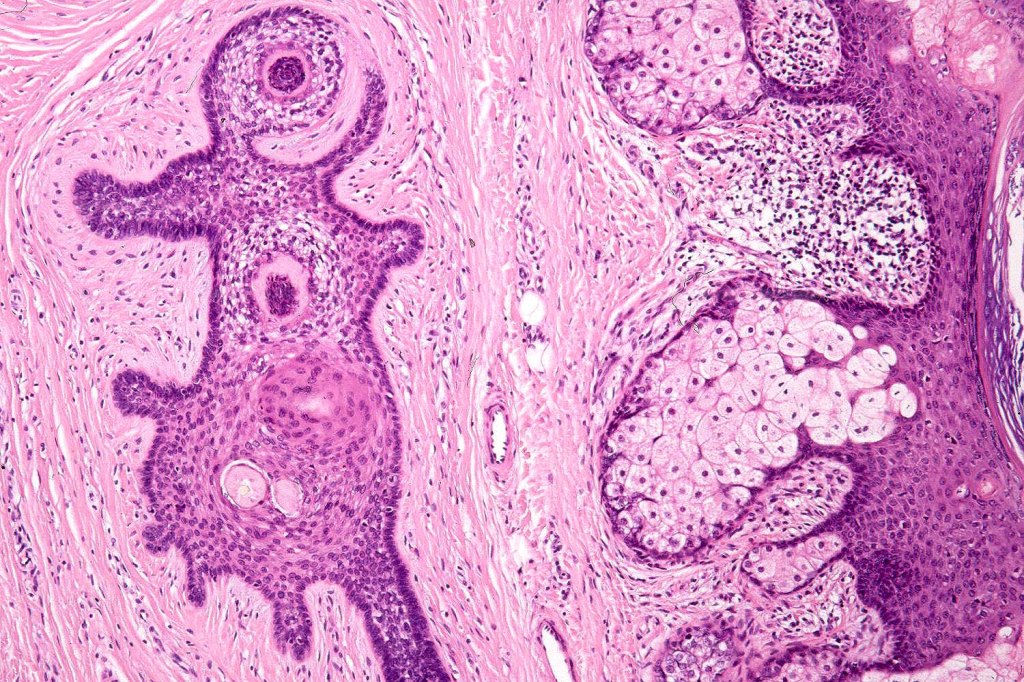

•Circumscribed dermal nodule with a characteristic silhouette

•An infundibular cyst is surrounded by laminated dermal collagen, elastic fibers, blood vessels, adipocytes & spindle cells separated from the adjacent dermis by a retraction artifact

•The cyst contains keratinous debris, and its wall shows conspicuous sebaceous & sometimes hair follicular elements are also evident

Folliculosebaceous cystic hamartoma can be distinguished from trichofolliculoma/sebaceous trichofolliculoma by the striking connective component and retraction artifact.